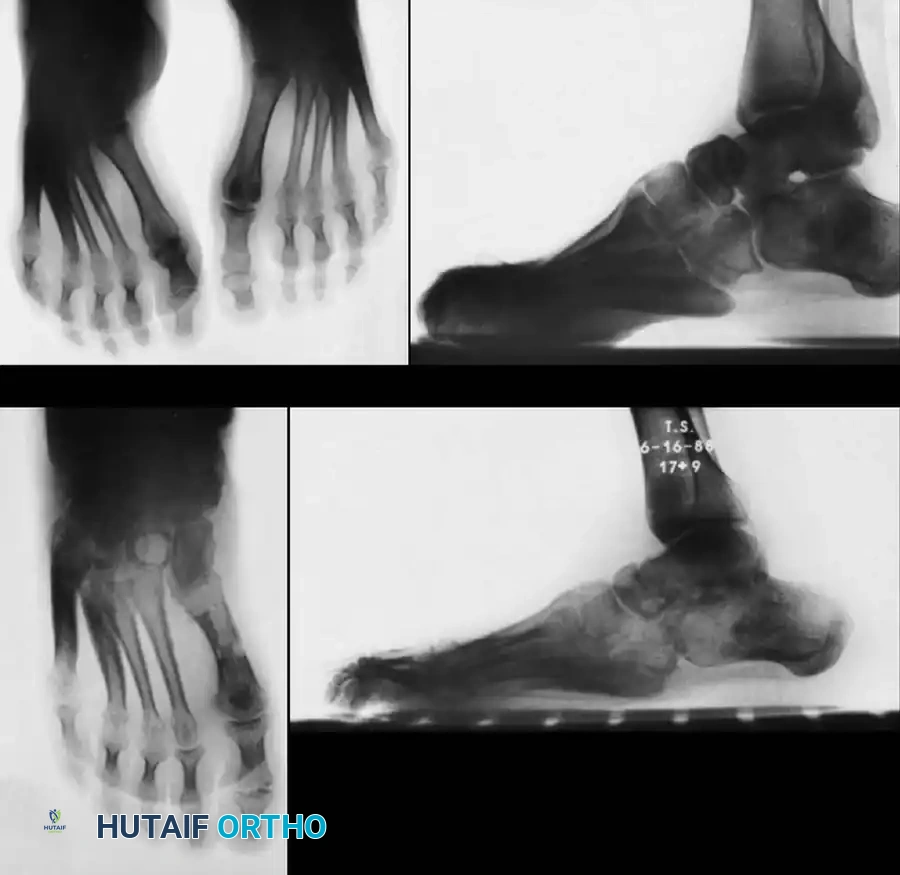

Fig. 32-20 Cavovarus deformity in Charcot-Marie-Tooth disease. A and B, Preoperative weight-bearing radiographs demonstrating severe cavus and hindfoot varus. C and D, Postoperative radiographs after triple arthrodesis, Achilles tendon lengthening, and posterior tibial tendon transfer.

Surgical Principles of Triple Arthrodesis in CMT:

* Deformity Correction: The Hoke arthrodesis (or a modification) is frequently utilized. Appropriate biplanar wedge resections are critical to correct the hindfoot varus and the midfoot component of the cavus deformity.

* Muscle Balancing: Arthrodesis alone is insufficient. Soft-tissue release and muscle balancing (e.g., transferring the strong posterior tibial tendon anteriorly through the interosseous membrane to the dorsum of the foot) are mandatory to prevent recurrence of the deformity and eliminate the need for a postoperative ankle-foot orthosis (AFO).

* Achilles Tendon Lengthening (ATL): McCluskey, Lovell, and Cummings emphasize that ATL should be performed after the forefoot and midfoot are corrected. Performing an ATL too early in the procedure can result in the force used to dorsiflex the forefoot inadvertently dorsiflexing the calcaneus into an unacceptable calcaneus deformity.

Fig. 32-21 Clinical appearance of the foot in Fig. 32-20 after triple arthrodesis, Achilles tendon lengthening, and posterior tibial tendon transfer. A, Anterior view showing restored alignment. B, Medial correction of the cavus arch. C, Posterior correction of the hindfoot varus to a neutral, stable weight-bearing axis.

Outcomes: When combined with appropriate tendon transfers, triple arthrodesis yields excellent long-term results in severe CMT. Wukich and Bowen reported good or excellent functional outcomes in 88% of their patients treated with triple arthrodesis and concurrent posterior tibial tendon transfer, successfully producing a painless, stable, and plantigrade foot.